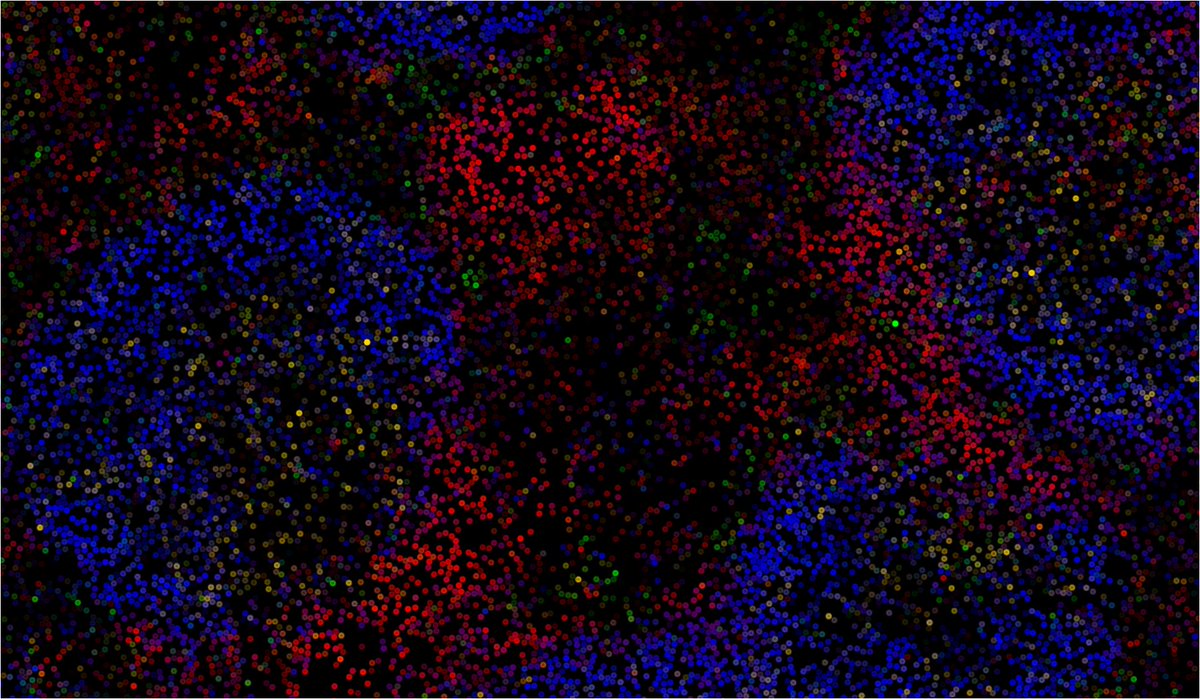

We discovered that aberrant BMI-1 in B cells is key for poor antibody in chronic infection.

Targeting BMI-1 improved Ab quality & viral clearance @MonashBDI